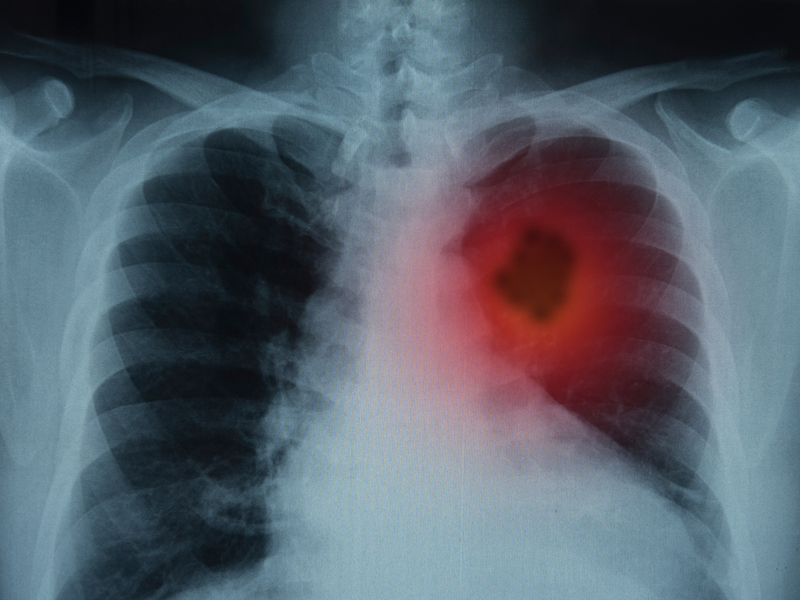

肺部有癌,雙腳先知?同時出現 4 現象,癌症或已到了中晚期